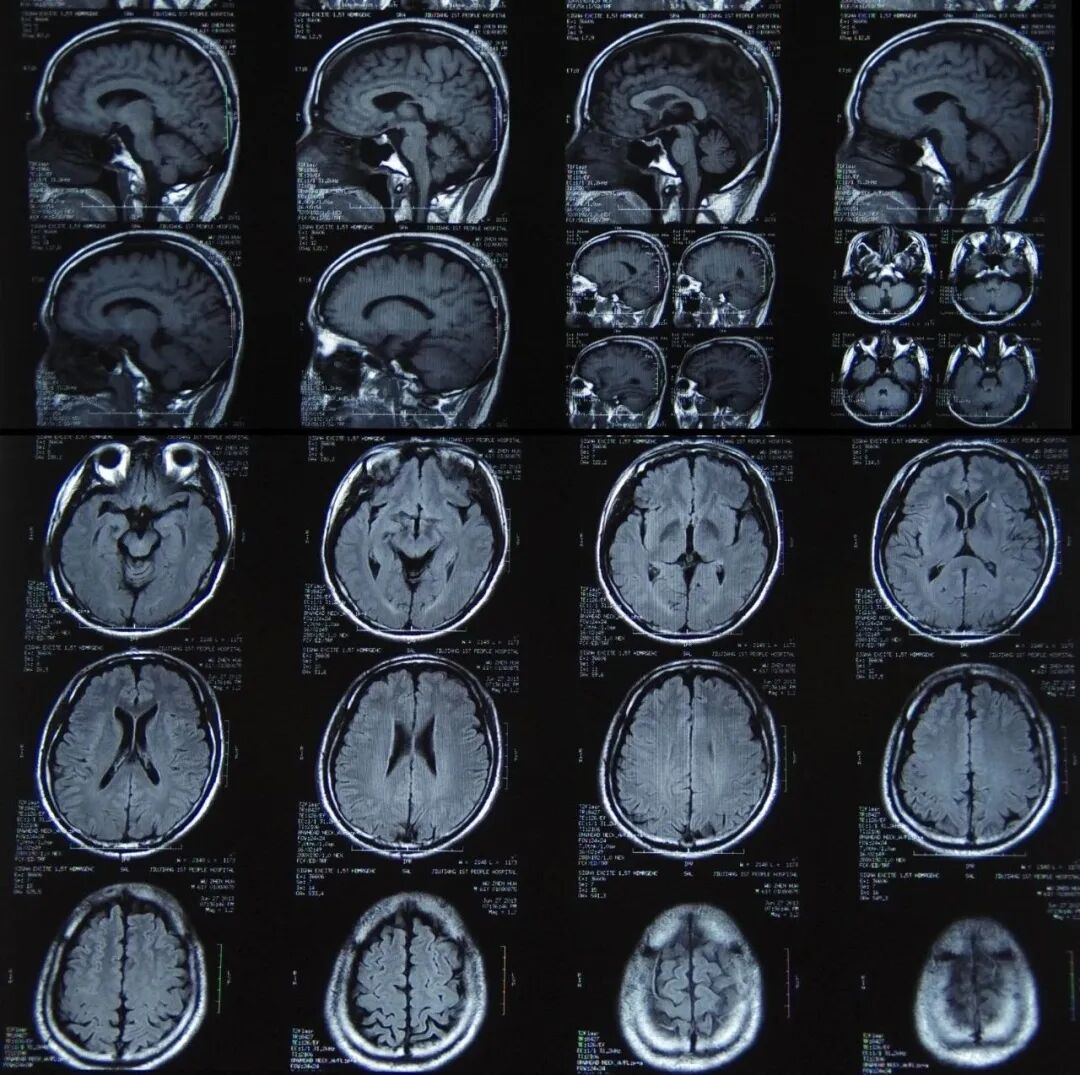

# 核磁(MRI、核磁共振) #

# 核磁共振检查是什么 #

核磁共振成像又称自旋成像,也称磁共振成像,简称MRI,是利用核磁共振原理,依据所释放的能量在物质内部不同结构环境中不同的衰减,通过外加梯度磁场检测所发射出的电磁波,即可得知构成这一物体原子核的位置和种类,据此可以绘制成物体内部的结构图像。

将这种技术用于人体内部结构的成像,就产生出一种革命性的医学诊断工具。快速变化的梯度磁场的应用,大大加快了核磁共振成像的速度,使该技术在临床诊断、科学研究的应用成为现实,极大地推动了医学、神经生理学和认知神经科学的迅速发展。

通俗来讲:

核磁共振仪是用强大的磁场让身体里的氢原子先排好队再解散,接收这段时间的电磁波信号,再给身体内部画像。相当于用手摇一摇,让水分子振动起来,再平静下来,成像。

核磁共振的作用

核磁共振成像是一种利用核磁共振原理的最新医学影像新技术,对脑、甲状腺、肝、胆、脾、肾、胰、肾上腺、子宫、卵巢、前列腺等实质器官以及心脏和大血管有绝佳的诊断功能。

与其他辅助检查手段相比,核磁共振具有成像参数多、扫描速度快、组织分辨率高和图像更清晰等优点,副作用很小,不具有辐射,可帮助医生“看见”不易察觉的早期病变,目前已经成为肿瘤、心脏病及脑血管疾病早期筛查的利器。